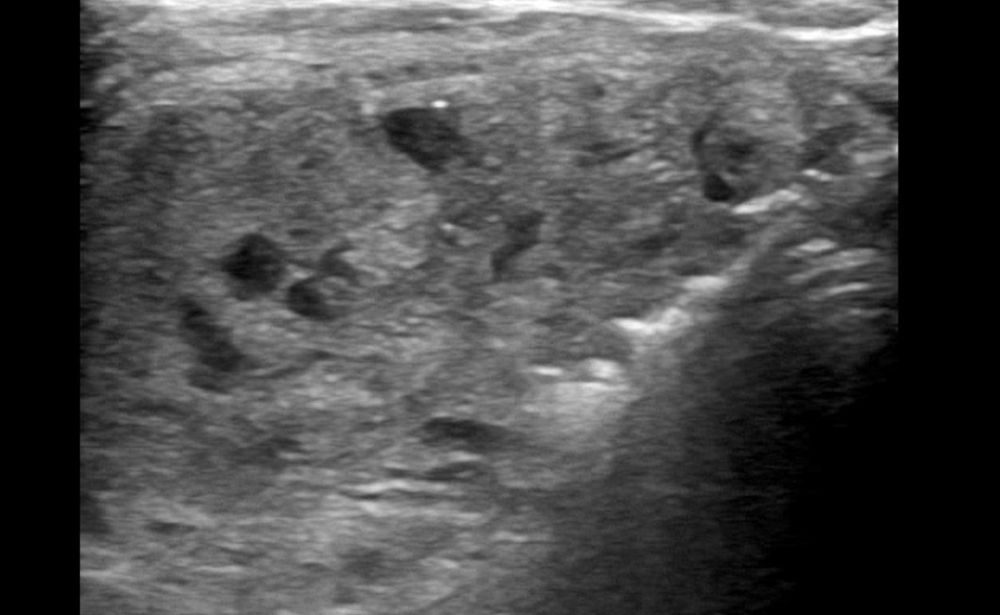

1. Thyroid Nodule Ablation (RFA/MWA)

The Problem: Benign thyroid nodules can cause uncomfortable symptoms like a visible lump in the neck, difficulty swallowing, or breathing problems.

Our Solution: A needle-thin probe is guided into the nodule using ultrasound. Radiofrequency (RFA) or Microwave (MWA) energy is then used to heat and destroy the nodule tissue, causing it to shrink significantly over time.

Patient Benefit: Avoids thyroid surgery and its associated risks, like a permanent scar and potential lifelong hormone medication. It is a daycare procedure.